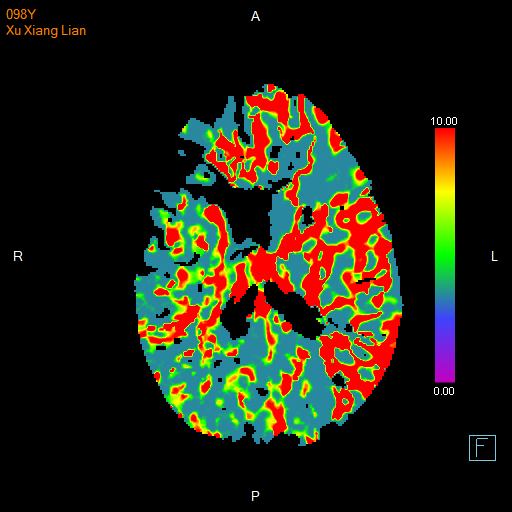

进一步的血管检查(CTA+CTP)发现了更严重的问题:王奶奶的左侧颈内动脉完全闭塞——这是脑梗中最凶险的类型之一,意味着大脑主要供血通道被切断,随时可能危及生命

颅脑 CTP